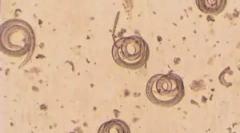

Ako vyzerajú takéto červy? Tento typ parazitov má špeciálne prísavky, s pomocou ktorej je červ pevne pripojený k tkanivám. Helmintes majú ploché telo a dosahuje dĺžku 18 mm. Všetky majú 2 typy prísavníkov. Jeden sa nachádza na peritoneum a druhý v oblasti úst. Parazit má mierne špicatý formulár.

Cerves majú tráviace a prideľovacie orgány, vďaka ktorému sa vykonáva ich biologický cyklus. Na tele helmins, sú tu závoje, s pomocou ktorej je pevne spojená s telesnou sliznicou. Jedinečnosť parazita je prítomnosť oboch genitálnych označení okamžite. Zároveň má ženské a mužské chovné orgány.

Počas dňa sú červy odložené na 900 vajec. Čo je charakteristické, sa nepodpokojujú, padajú do ľudského tela. Tam, akumulujú sa len vďaka rybám jedlé. Vajcia môžu očakávať takmer rok v riečnej vode, na základe ich životného obdobia je výrazne menej. V pôde sa spolu s výkalmi. Vajcia pre človeka nie sú nebezpečné. Orgány sú pre nich len medziproduktový cyklus.